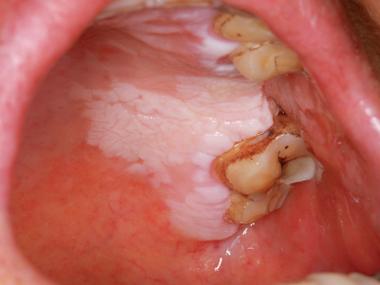

口腔腮帮子有条白棱是何问题?

(图片来源网络,侵删)

- 表面粗糙,呈白色或灰白色,形态不一,可以是斑块、皱纹状或颗粒状。

- 典型的表现是“珠光白色条纹”或“网状白纹”,像“蕾丝花边”一样,有时也会表现为白色斑块或丘疹。